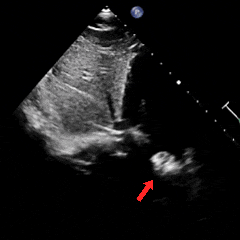

经胸右心声学造影:经左肘静脉注入震荡生理盐水(8mL生理盐水+1mL回抽静脉血+1mL空气经震荡制成),上腔、右房依次显影,造影剂完全充盈右心后,平静呼吸时,左房内即可探及微泡回声,约20-30个/切面/帧;瓦氏呼吸释放即刻,左房内探及微泡回声,不可计数。

术前静息状态经胸右心声学造影(中量)